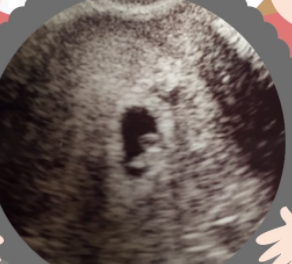

6週1日(6w1d・男の子)|まめたくん さん(28歳)

エコー写真撮影時のエピソード:

つわりがはじまっていて、毎日しんどかった。なんどもくじけそうになった。 でも一方でほんとに赤ちゃんがきてくれてるのか、とっても不安だった。

初エコーで心臓ぱくぱく動いてるのが見え、赤ちゃんが生きてる!ってことに感動した。